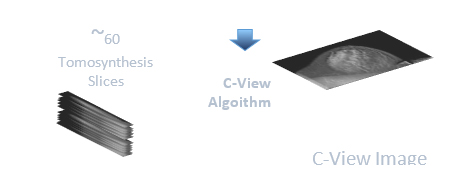

H αδιαμφισβήτητη υπεροχή του SELENIA DIMENSIONS έναντι άλλων ψηφιακών μαστογράφων επισφραγίζεται από την πιστοποίηση EUREF. Ο ψηφιακός μαστογράφος SELENIA DIMENSIONS έλαβε την πιστοποίηση “MammographicTypeTest” από τον Ευρωπαϊκό οργανισμό EUREF(European Reference Organization). Η εν λόγω πιστοποίηση προϋποθέτει ιδιαίτερα απαιτητικά test κλινικής και φυσικής λειτουργίας ώστε να συμβαδίζει με τα σχετικά πρότυπα ποιότητας εικόνας, έκθεσης ακτινοβολίας και standards σταθερότητας, όπως αυτά ορίζονται από τον οργανισμό EUREF, ενώ χορηγείται δυσκολότερα από την πιστοποίηση CE Mark. - Ο ψηφιακός μαστογράφος ΤΟΜΟΣΥΝΘΕΣΗΣ που λειτουργεί στο κέντρο μαστού διαθέτει την πρωτοποριακή εξέλιξη της τεχνικής Τομοσύνθεσης και εγκεκριμένη από FDA τεχνική C-VIEW (Synthesized 2DMamography) , μέσω της οποίας η δόση ακτινοβολίας και ο χρόνος εξέτασης μειώνεται στο μισό.

Με την επαναστατική τεχνική C-VIEWTM εξαλείφεται πλήρως η ανάγκη για την λήψη 2D ψηφιακής μαστογραφίας καθώς μέσω της 3D λήψης δημιουργείται η synthesized 2D εικόνα του ίδιου μαστού η οποία απεικονίζει ευκρινέστερα όλες τις χρήσιμες πληροφορίες και δομές μιας 2D εξέτασης.

Πρέπει επίσης να επισημανθεί ότι δεν είναι όλες οι τεχνικές συνθετικής 2D μαστογραφίας πιστοποιημένες στο να αντικαταστήσουν ισάξια την 2D εξέταση. Η συνθετική μαστογραφία C-VIEWTM της HOLOGIC διαθέτει ξεκάθαρα την μοναδική κλινική ένδειξη από τον FDA προκειμένου να αντικαταστήσει την 2D εξέταση σε έναν μαστογραφικό έλεγχο και να χρησιμοποιηθεί μεμονωμένα για να παρέχει μία αξιόπιστη διάγνωση.